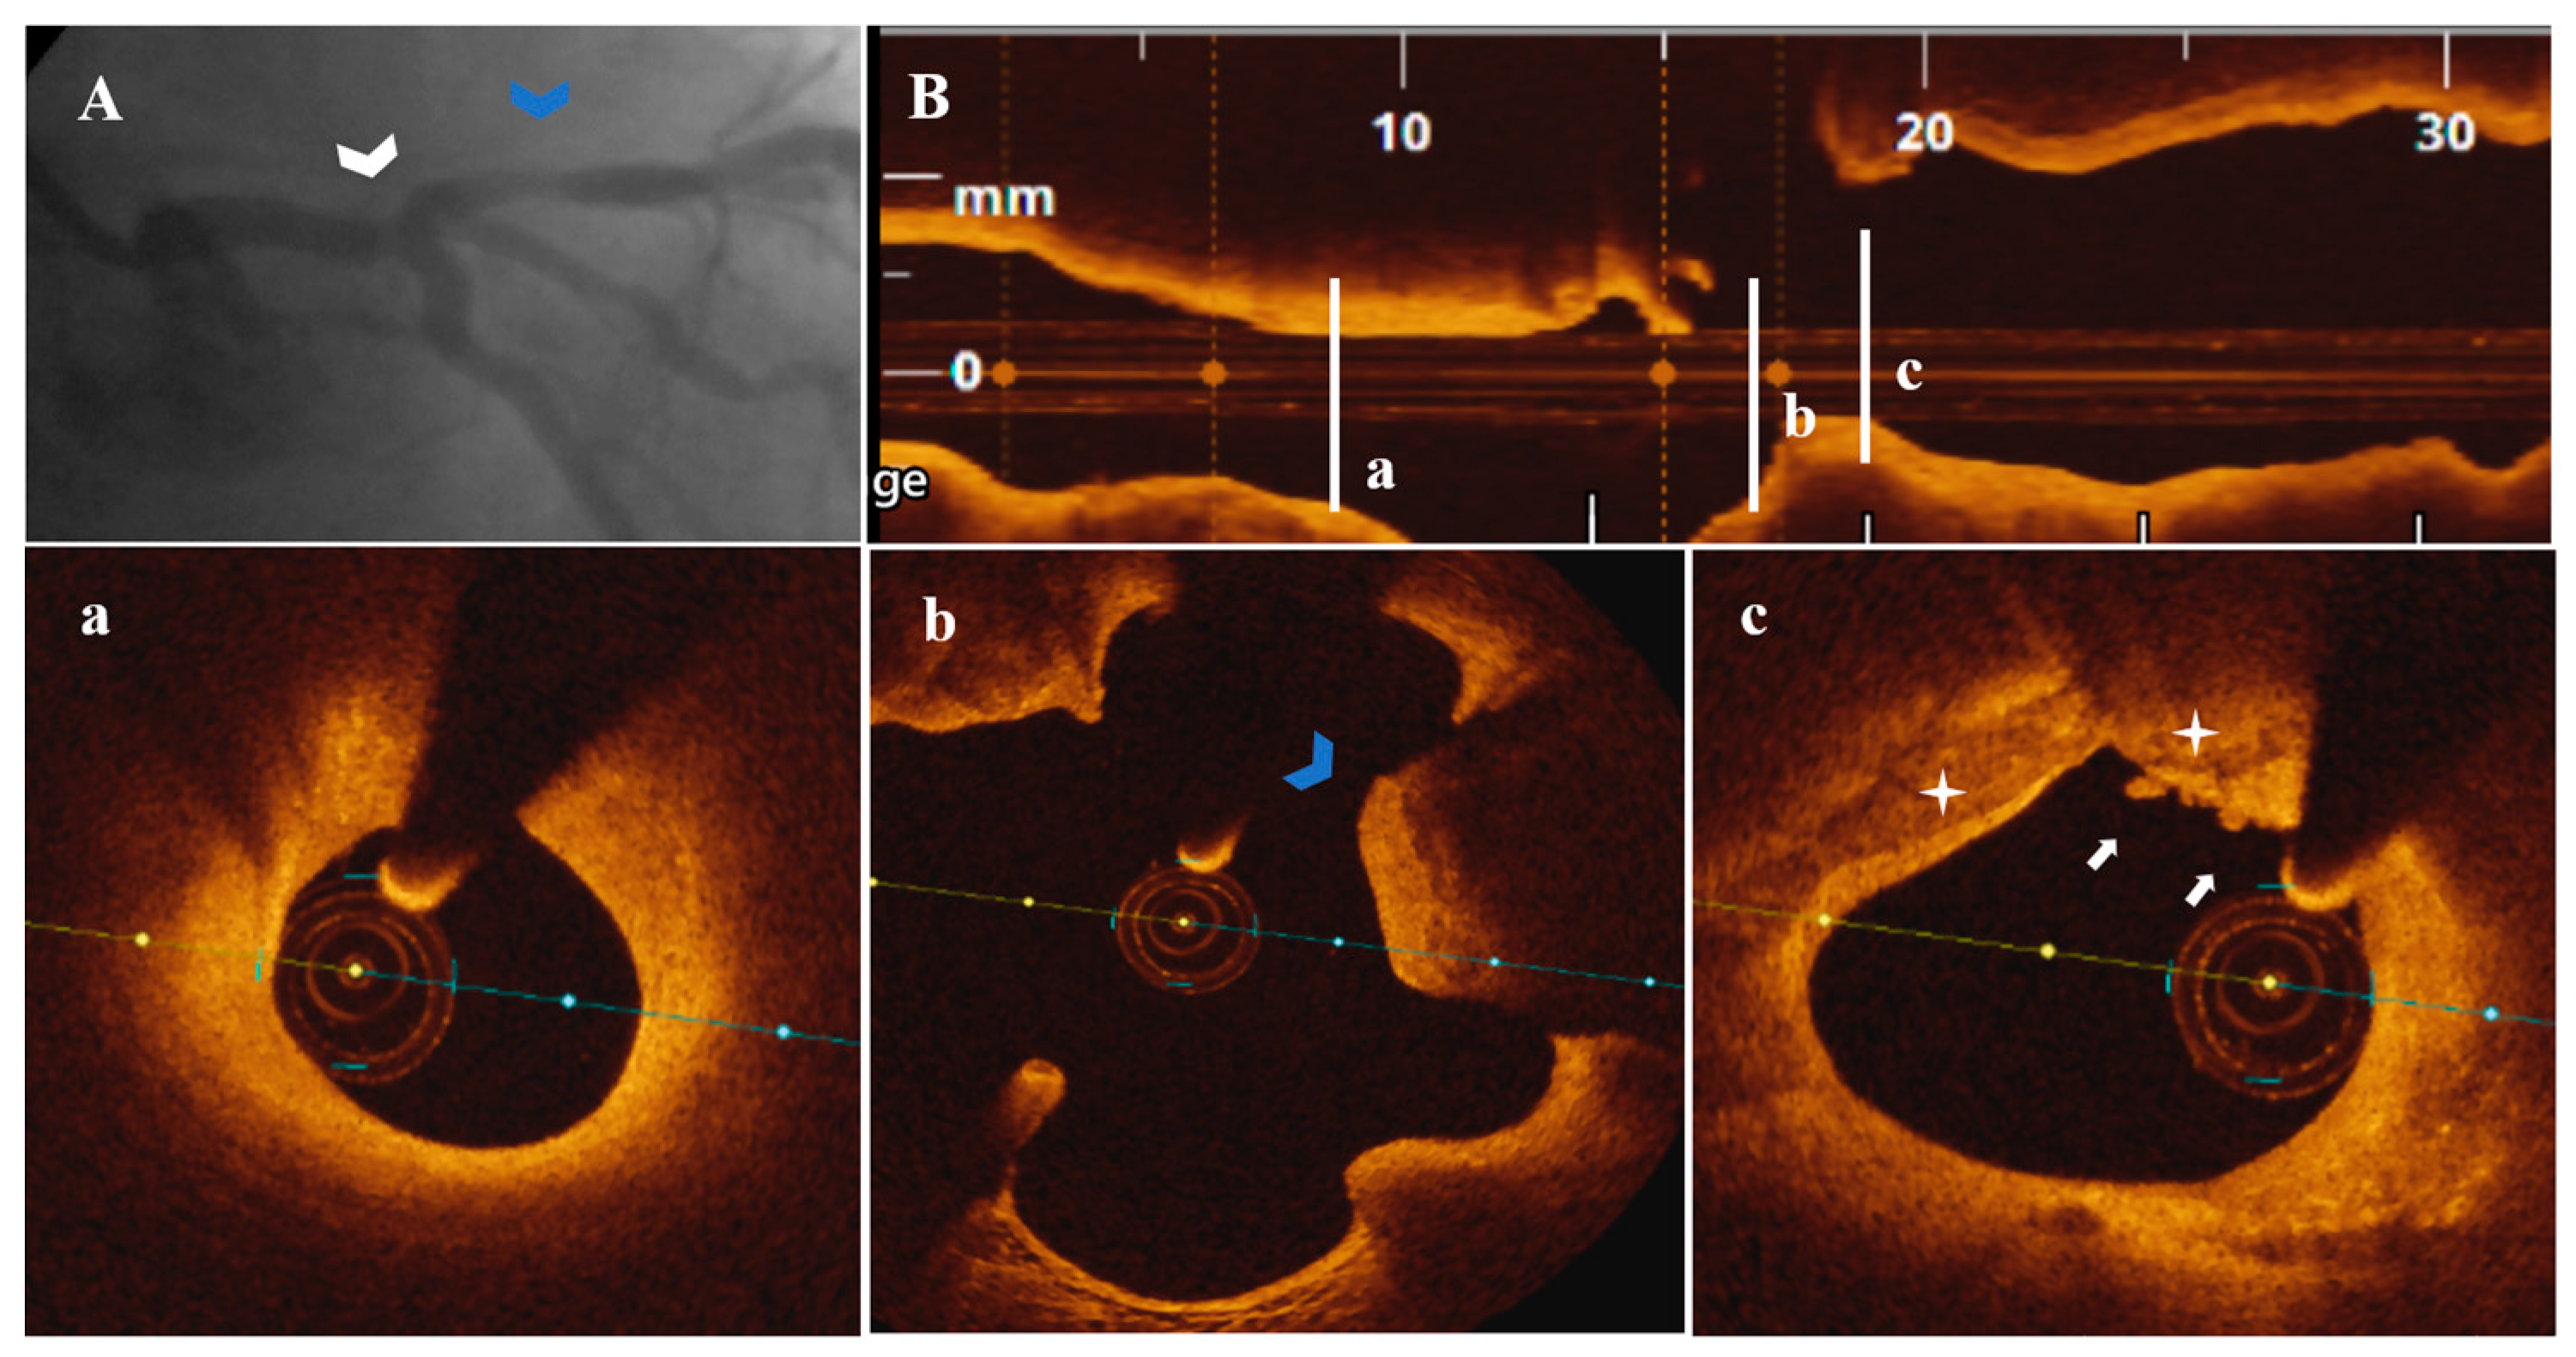

Figure 6.

A 58-year-old patient presenting with NSTEMI. (A) CA—borderline proximal LAD stenosis (white arrowhead), severe first diagonal ostial stenosis (blue arrowhead). (B) OCT—LAD plaque longitudinal view. (a–c) Significant LAD lesion (area stenosis = 74.6%) presenting PE with white thrombi (white arrow) on SCP (white star) extending distally into the ostium of the first diagonal and proximally in interrelation with a healed plaque (blue arrow).